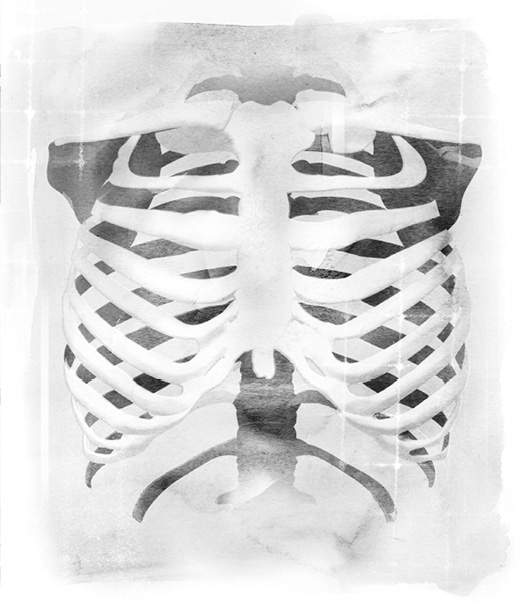

◆胸廓

胸廓的形状有如蜂窝,它包围、保护着体内最重要的维生器官—心脏和肺脏,并且使胸部的骨架保持稳定。胸廓几乎跟所有肋骨都互相连接,为每一根肋骨提供支撑力。人体总共有二十四根肋骨,每边各十二根,连接着身体背面的脊椎与正面的胸骨。肋骨和脊椎是借由胸椎关节串接起来,胸椎关节的巧妙设计让它可以随着每一次呼吸而自由活动。

有了这些可滑动的关节,整个胸廓便可以自在、轻松地活动。软骨把身体正面的肋骨结合在一起,这些软骨使得胸廓具有足够的强度,同时又富有弹性,可以顺应吸进来的空气多寡而适当地活动。人体的肋骨生来就具备弹性和可活动性,因为它们必须让内部的肺脏可以活动自如。

胸骨是一根长而扁的骨头,垂立在胸腔正面的中央,大约长十五公分、宽二.五公分,呈垂直状。它分为三个部分,功能是支持大多数的肋骨,并且保护气管不受伤害。上方的七根肋骨直接与胸骨相连,接下来的三根肋骨则是借由弧形的肋软骨,附着在胸骨上。剩下的二根肋骨称为漂浮肋骨,因为它们根本没有跟胸骨连接在一起,而是「漂浮」着,附着在身体背部的脊椎上。

当身体运作顺畅的时候,呼吸系统的肌肉和骨骼全部可以自由活动,彼此协调合作。如果身体内的肌肉过于紧绷,就会妨碍到直立、富有弹性,却又微妙平衡的骨架结构。这种肌肉紧绷会让胸腔周围的部位变得僵化,妨碍到呼吸系统天生的运作设计,使得原本毫不费力的呼吸动作变得大为吃力。